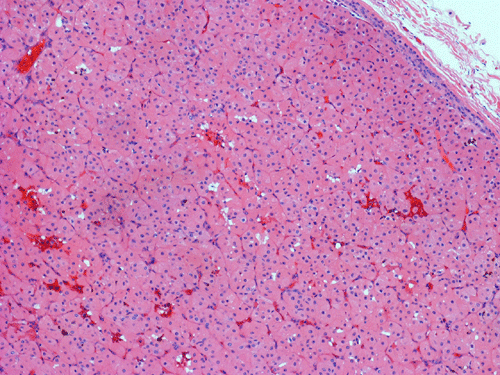

Pathology of the Case: Grossly, the tumor was a small 1 x 2 cm well demarcated nodule embedded within the mid portion of the salivary gland. There is no true capsule (Panel A). The tumor cells arrange in solid sheets and without specific pattern formation (Panel B and C). There is no collagenous tissue within the tumor. The tumor cells are polygonal and rather homogeneous in size. They have low-grade, centrally located nuclei (Panel D), finely granular and distinctly eosinophilic cytoplasm. The granular feature is best appreciated in the cytoplasmic preparation that is prepared while the tumor is being examined before fixation (Panel E).  There is no necrosis or mitotic figures.

Grossly, oncocytomas are well-circumscribed, well-demarcated, round to lobulated nodules, averaging 3-4 cm in size. Oncocytomas arising from major salivary glands are usually encapsulated and those arising from minor salivary glands have less well defined borders and are usually not encapsulated. The cut surface has a typical tan-brown color. Benign oncocytomas frequently have with a central star-like scar.

Microscopically, oncocytes have a very characteristic appearance with granular eosinophilic cytoplasm due to marked increase in the number of mitochondria mitochondria, pleomorphism of mitochondria, and a paucity of other organelles. The tumor cells have little variation among different tumors or different part of the same tumor. Characteristically, the tumor cells are rather uniform and polygonal in shape. The cytoplasmic membrane can be readily recognized. The nuclei are usually round, centrally located, and nucleoli are present. The cells are arranged in uniform solid sheets without a specific pattern  or they may aggregate into clusters, and sometimes they form duct-like structures. Thin fibrovascular septa are present. Oncocytomas may have a clear cell component secondary to accumulation of cytoplasmic glycogen 6. A PAS stain with and without diastase digestion will be very helpful in recognizing the glycogen. High grade nuclear atypia is only seen exceptionally. Phosphotungstic acid hematoxylin (PTAH) is a good stain that would stain the mitochondria dark. However, the stain is rarely called to service for this purpose as the cytoplasm is typically characteristic enough for recognition without special stain. In clear cell variants, however, PTAH may help. Mitotic figures are not readily seen. In most situations, the diagnosis of oncocytoma is not a particularly challenging one.